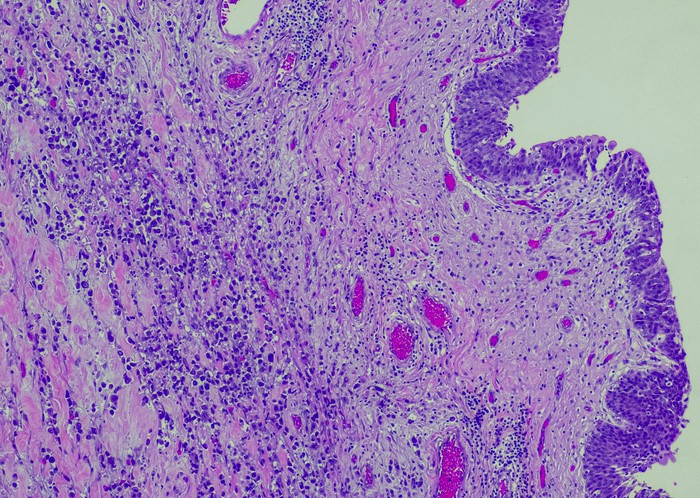

Featured photo at top of urothelial carcinoma cells stained purple. Photo/OGPhoto/iStock.